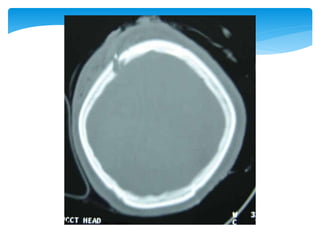

Approach To CT ScanCT scan

Bone window

Look for fractures-

•Cranial vault

•Skull base

•Facial bones

Approach To CTScanCT scan Bone window Look for fractures- •Cranial vault •Skull base •Facial bones Tissue window •EDH •SDH •ICH •Contusions •Pneumocephalus •Hydrocephalus •Cerebral edema Subdural window •Any hemorrhage •Soft tissue and bone •Fontanel •Suture lines •Foreign bodies

• 52.

 Appearance ofthe normal structures CT Scan